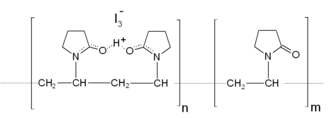

| Molecuulformule | (C6H9NO)n·xI | |||

| IUPAC-naam | polyvinylpyrrolidon-joodcomplex | |||

Chemisch gezien is het een gecomplexeerde vorm van jood, waarbij dat element zich bevindt in een lange keten van vele polyvinylpyrrolidon-ringen. Daarbij wordt gemiddeld één op de twintig plekken tussen de ringen ingenomen door een joodatoom. Dit complex zorgt voor een gecontroleerde afgifte van vrije di-joodmoleculen, die een breed spectrum van micro-organismen, zoals bacteriën, virussen en schimmels, kunnen doden.